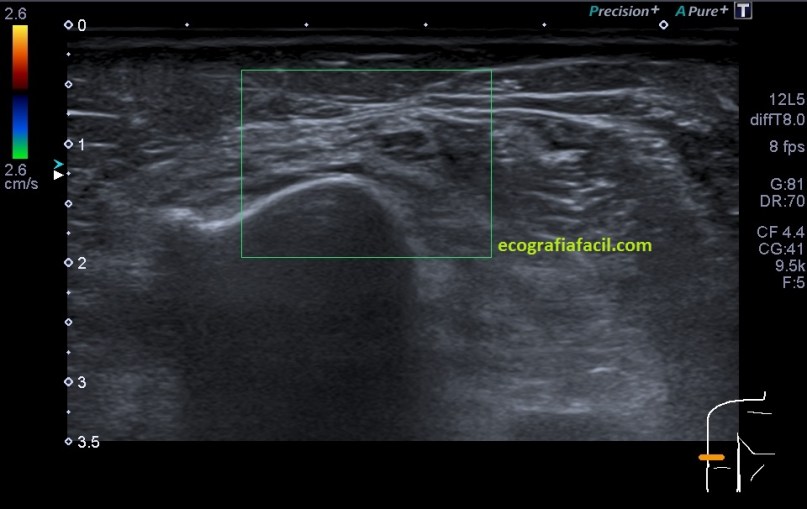

El nervio afectado por la neuropatía es avascular tanto el doppler como en el modo angio.